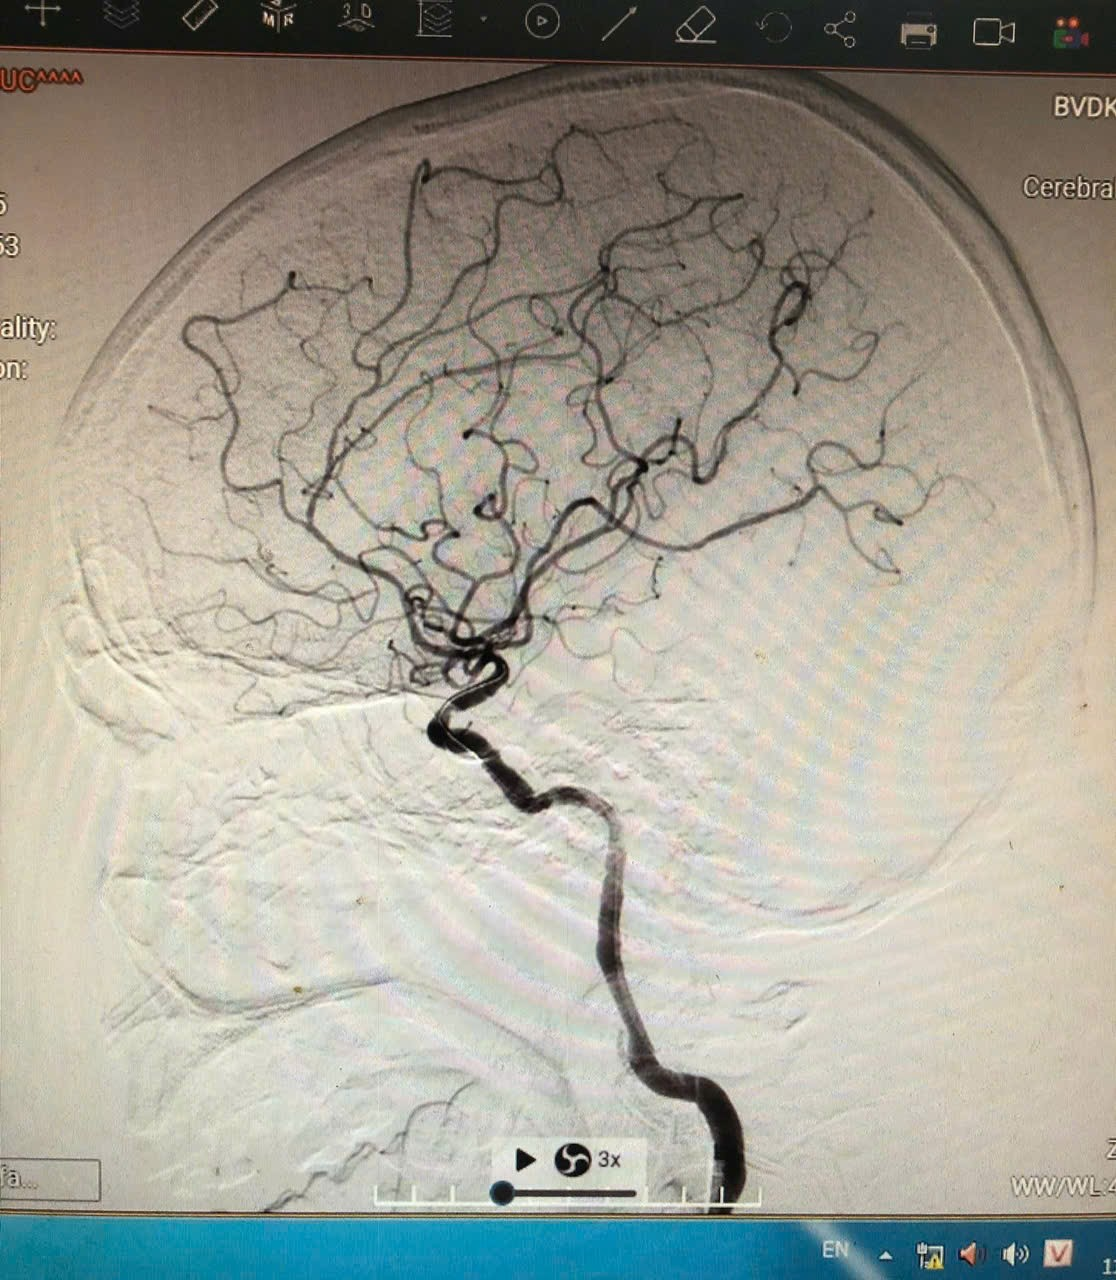

![]() |

| Hình ảnh chụp mạch máu não kỹ thuật số xóa nền (DSA) cho thấy hệ thống động mạch não bên trái được tái thông hoàn toàn sau can thiệp, dòng chảy máu lên các nhánh não rõ nét và liên tục |

Kết quả cho thấy, bệnh nhân bị tắc nhiều đoạn động mạch cảnh trong trái, đồng thời hẹp nặng động mạch não giữa cùng bên. Quy trình can thiệp mạch máu não được kích hoạt khẩn cấp. Trong vòng 1 giờ, các bác sĩ đã tái thông hoàn toàn động mạch cảnh, khôi phục lưu thông máu não.

Diễn biến hồi phục của bệnh nhân hết sức khả quan: chỉ vài giờ sau can thiệp, điểm NIHSS giảm từ 22 xuống còn 15; sau 3 ngày, bệnh nhân đã nói chuyện được, thực hiện theo y lệnh và cử động tay chân một phần; đến ngày thứ 5, ông có thể đi lại, tự ăn uống và sinh hoạt đến 90%.